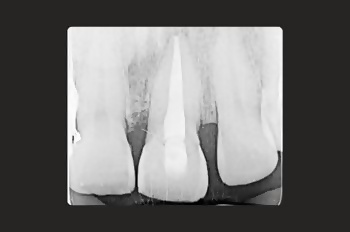

Root canal treatment is a restorative tooth-saving procedure that can avoid the need for an extraction.

Root canal treatments are a core aspect of endodontics, the dental speciality focused on treating infected tooth pulp and addressing complications from previous treatments.

Root canal treatment is needed when the tissues inside a tooth become damaged, infected, or inflamed due to deep decay, cracks, injury or repeated dental procedures on the same tooth.

Root canal treatment allows your dentist to remove the infection before it can cause irrevocable damage. It’s a tooth-saving procedure that very often saves a tooth from needing to be extracted.

Your tooth is disinfected and sealed, preventing further bacteria from compromising its structure and health.